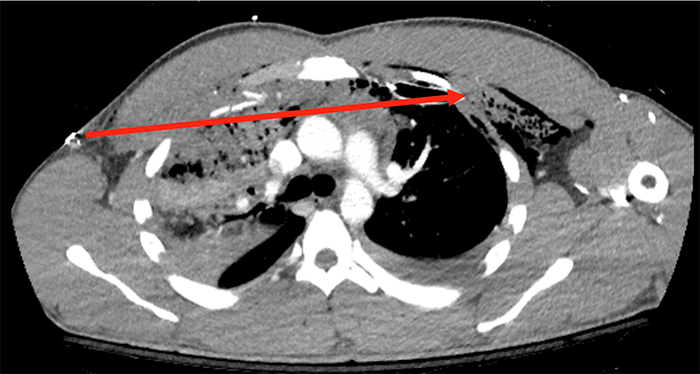

Given his clinical stability, we opted to send our patient for chest CT with intravenous contrast, which revealed a comminuted right second rib fracture, right upper lung contusion with trace right hemopneumothorax, anterior mediastinal hematoma, and left upper lung contusion with left hemothorax. There was no evidence of great vessel injury, active extravasation or pericardial effusion. The bullet was located much more inferiorly, in the left diaphragmatic sulcus at the left lung base. We believe that the bullet traversed both lungs and the superior anterior mediastinum (see red lines in Figure 2 and Figure 3), striking the left second rib and coming to rest in the pleural space along this trajectory. From there, the bullet apparently moved dependently within the pleural space and came to rest in the posterior sulcus.

Figure 3. Axial CT image of patient with Transmediastinal gunshot wound depicting the bullet trajectory. Solid red line depicts bullet trajectory based on tissue injury on CT scan.